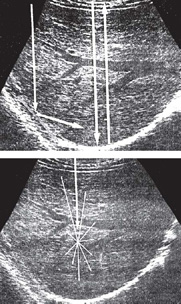

Another composite of attenuation is scattering. This type of scattering is also known as nonspecular or diffuse reflector and responsible for providing the internal texture of organ in image, e.g. lung and kidney parenchyma, red blood cells.

The scattering occur because these tissues (Fig. 1.6) represent a bumpy or rough surface and their sizes are smaller than the wave length of sound waves. The bumpy interface provides a multiple or non-perpendicular surface from which reflection occurs in all the directions causing a loss of intensity.

These surfaces are not very angle dependent as compared to the cases of specular reflector where if the beam is not perpendicular, to the surface of interface their echoes will not be recorded by the transducer. Where as in case of diffuse reflector, since sound wave is scattered in all the direction so some portion of echoes will also be recorded by the transducer. Effect of oblique, perpendicular incidence and diffuse reflection are represented in the Figures 1.7A and B.

Figs 1.7A and B: Specular and diffuse reflectors. Specular reflector. (A): The diaphragm is a large and relatively smooth surface that reflects sound like a mirror reflects light. Thus, sound striking the diaphragm at nearly a 90° angle is reflected directly back to the transducer, resulting in a strong echo. Sound striking the diaphragm obliquely is reflected away from the transducer, and an echo is not displayed (arrow). Diffuse reflector (B): In contrast to the diaphragm, the liver parenchyma consists of acoustic interfaces that are small in comparison to the wavelength of sound used for imaging. These interfaces scatter sound in all directions, and only a portion of the energy returns to the transducer to produce the image